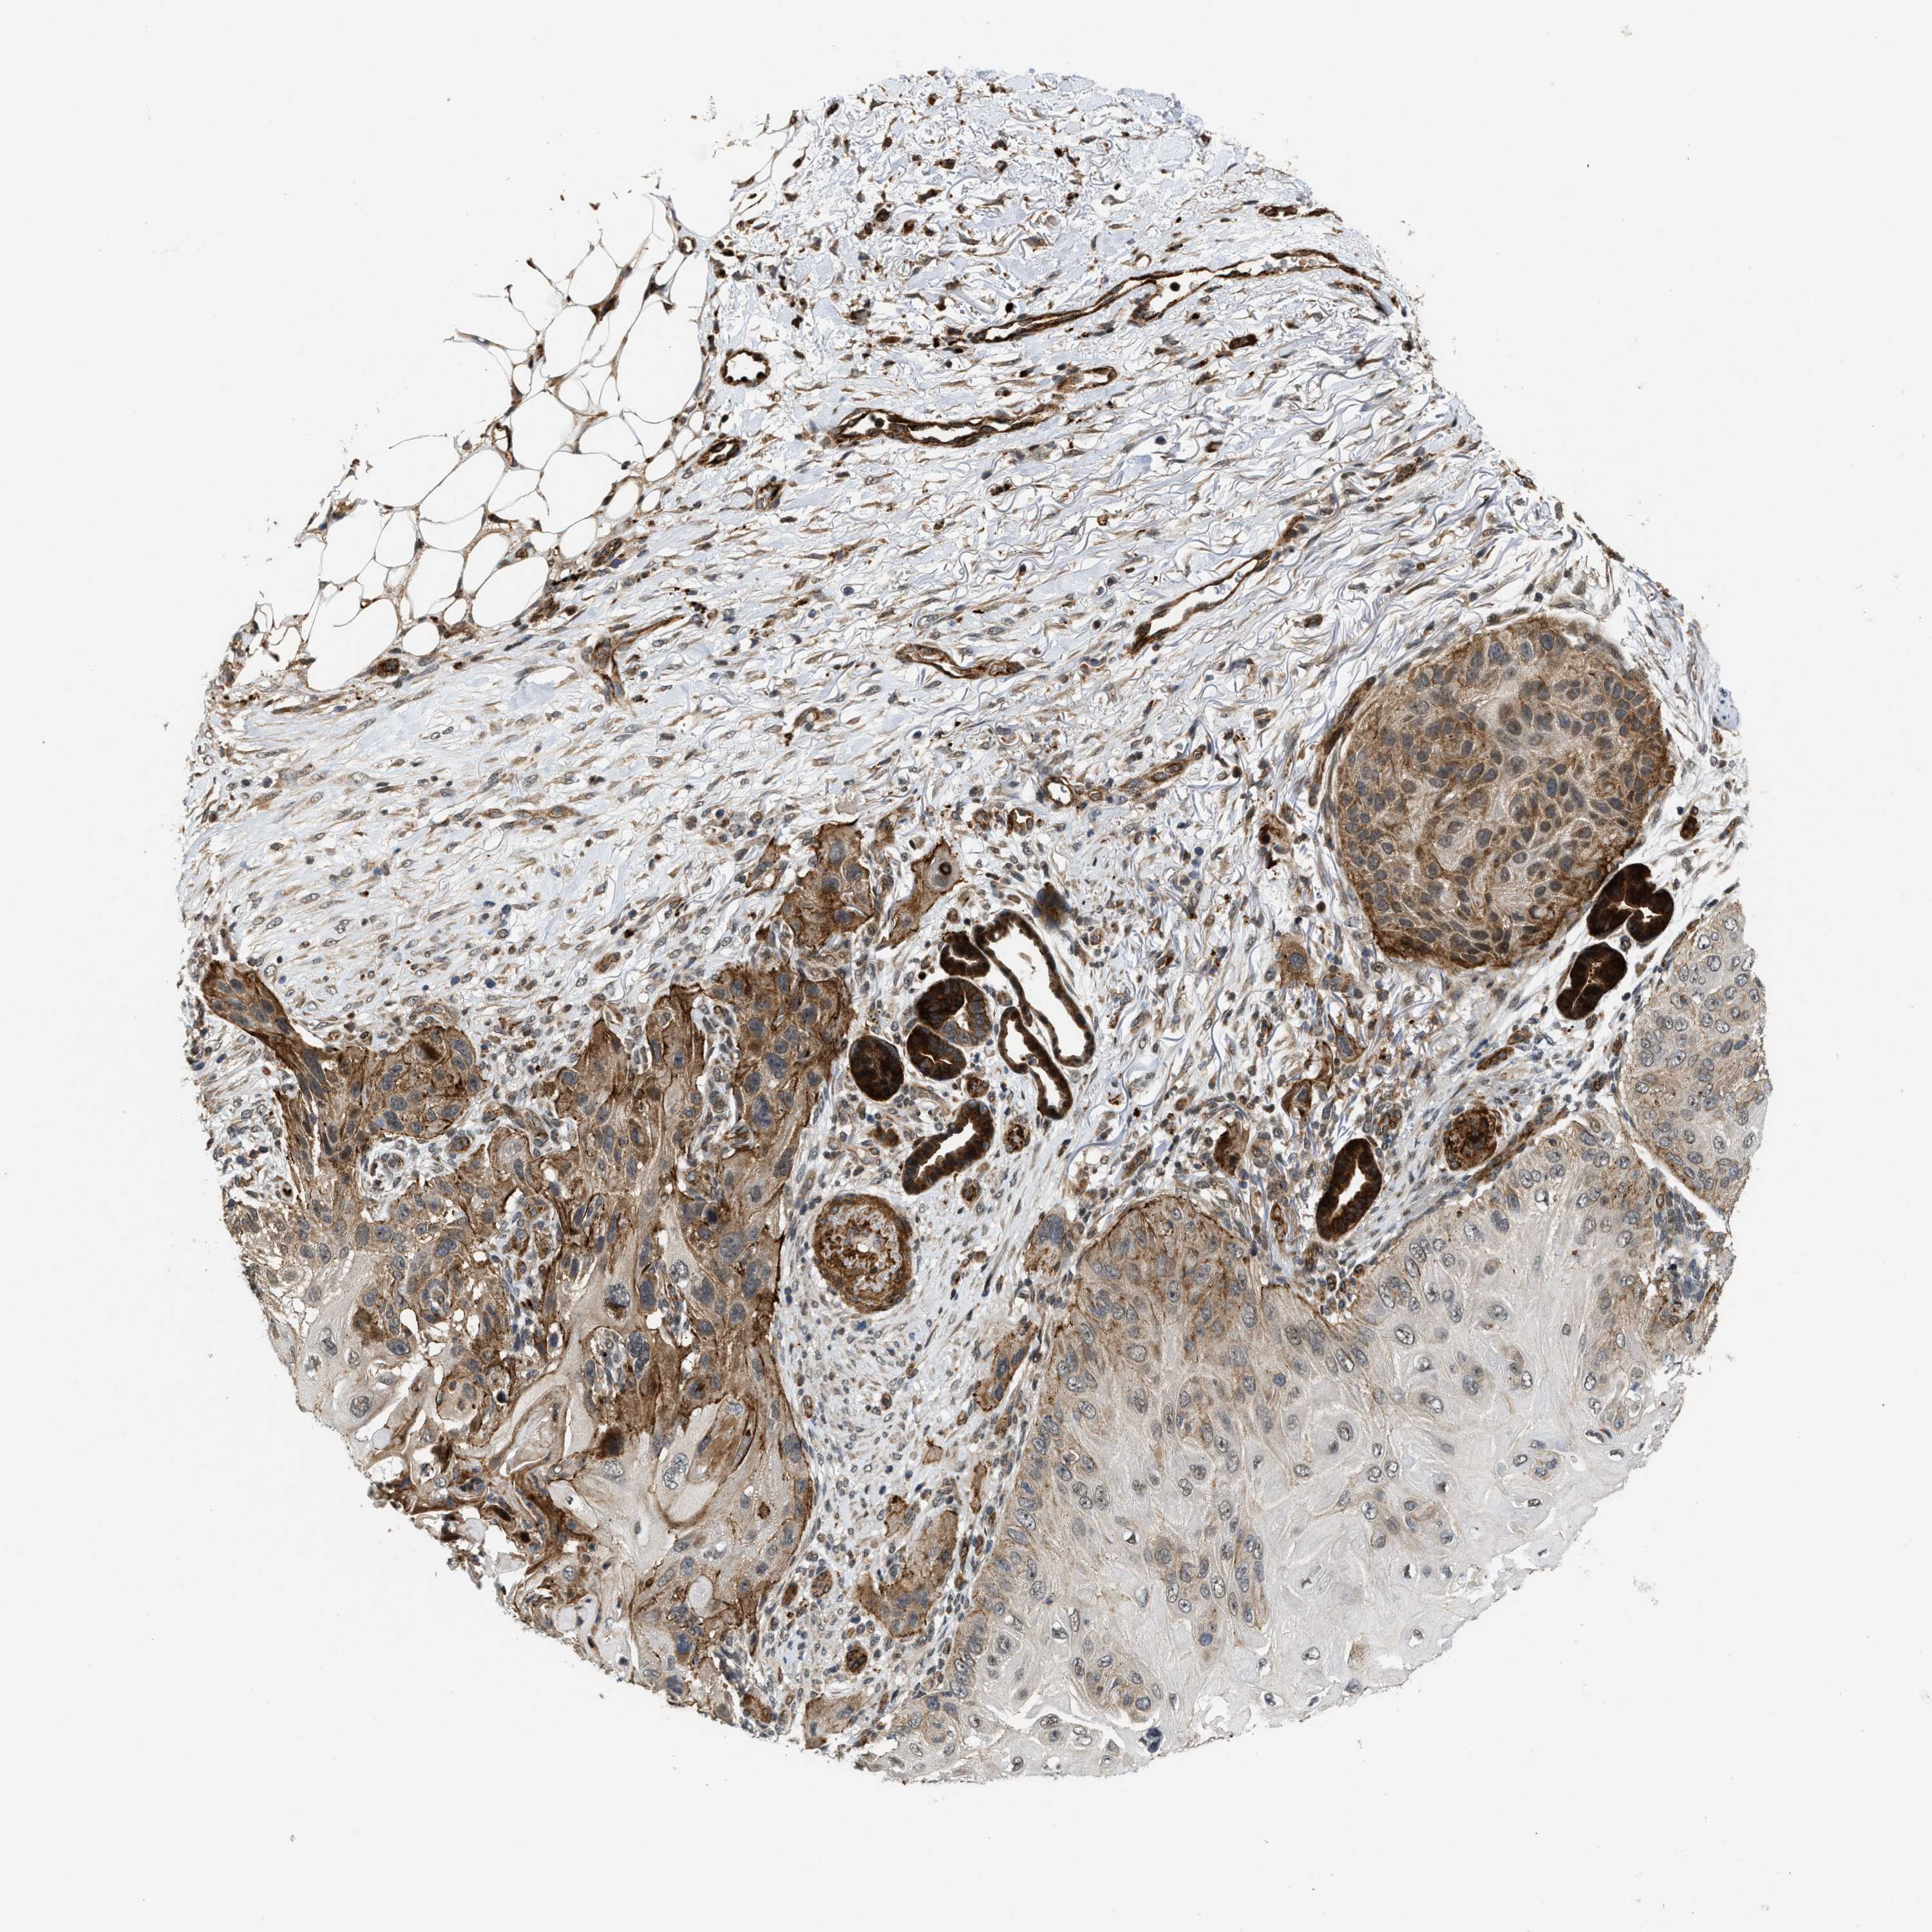

SKIN CANCER - Protein expressioni

A mouse-over function shows sample information and annotation data. Click on an image to view it in a full screen mode. Samples can be filtered based on level of antibody staining by selecting one or several of the following categories: high, medium, low and not detected. The assay and annotation is described here.

Antibody stainingi

Antibody staining in the annotated cell types in the current human tissue is reported as not detected, low, medium, or high, based on conventional immunohistochemistry profiling in selected tissues. This score is based on the combination of the staining intensity and fraction of stained cells.

Each image is clickable and will lead to virtual microscopy that enables deeper exploration of all samples and also displays staining intensity scores, fraction scores and subcellular localization as well as patient and tissue information for each sample.

Antibody HPA020880

Staining

High

Intensity

Strong

Quantity

>75%

Location

Nuclear

Basal cell carcinoma

Squamous cell carcinoma, NOS

Squamous cell carcinoma, metastatic, NOS